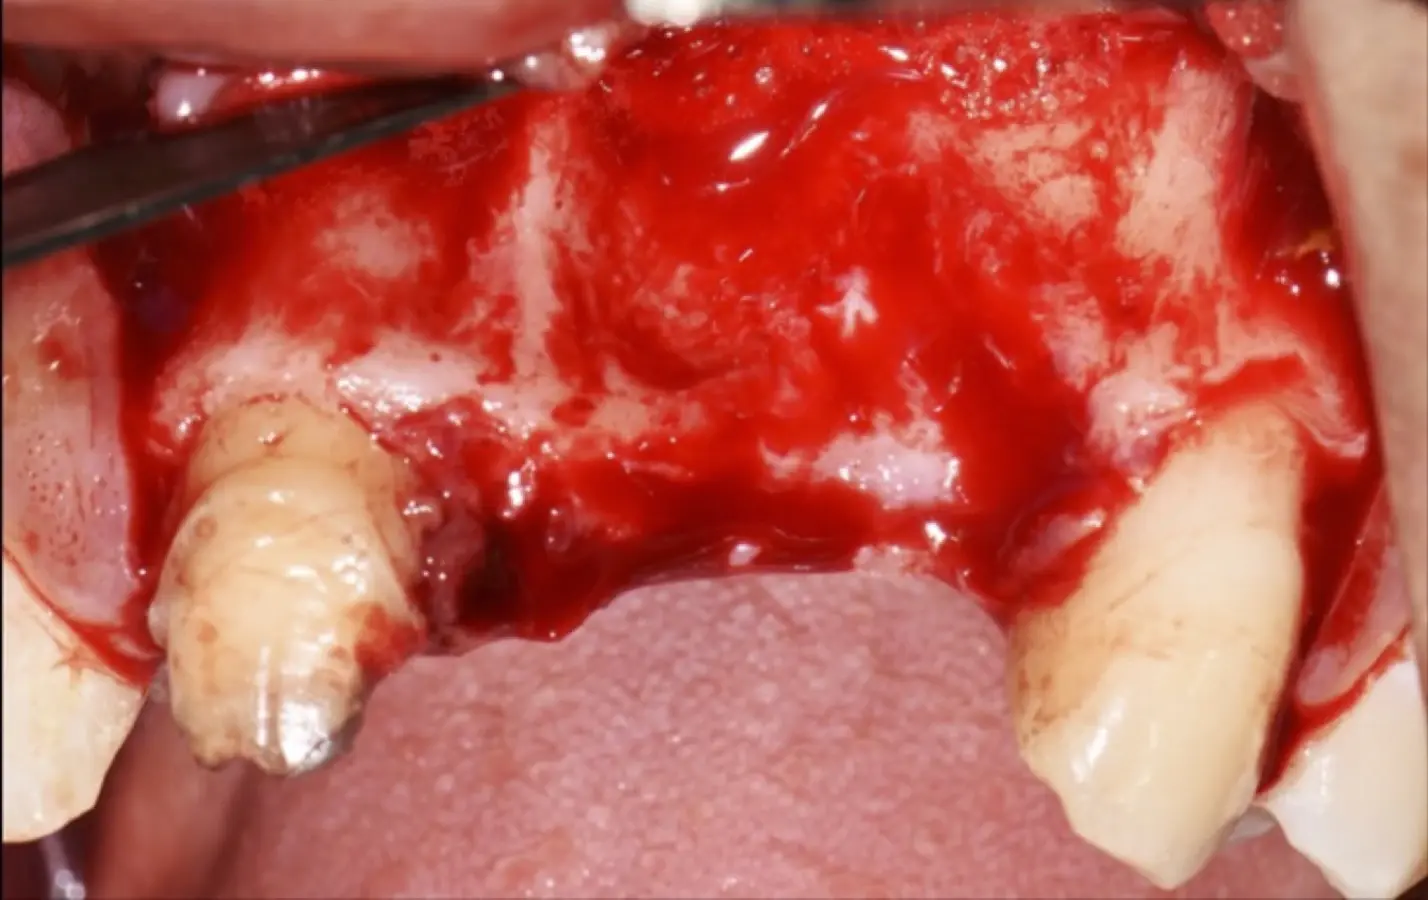

Figura 19. Tomografía computarizada de la zona receptora. Pieza 1.3 (a). Pieza 2.1 (b).